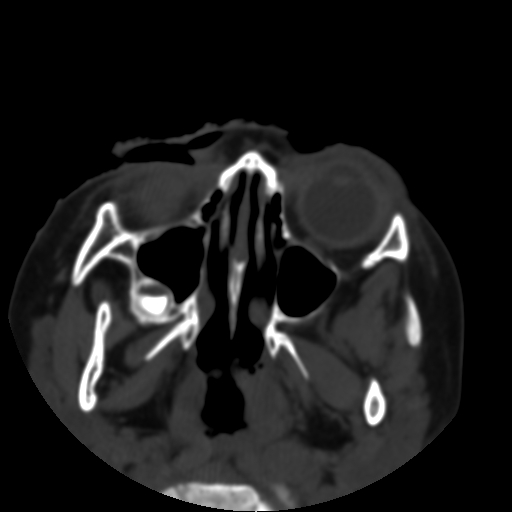

以下是引用深泽交通医院在2009-10-16 8:25:00的发言:[br]右眼环出血伴异物

以下是引用拾荒者在2009-10-17 18:38:00的发言:[br]鼻面部皮下积气,右侧睑缘及眼球壁高密度异物影,左侧眼球壁晶状体内侧缘处是圆形低密度影。低密度异物?应提请眼科医生注意。